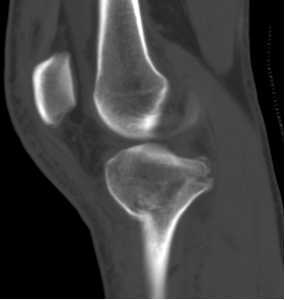

胫骨平台是位于胫骨上端的一个平台,与股骨的髁部形成膝关节。胫骨平台骨折是指胫骨平台部位发生的骨折,可能是由于直接撞击、跌倒或扭伤等原因引起。根据骨折的严重程度和位置,可分为多种类型,如单纯骨折、粉碎性骨折等。

胫骨平台关节面塌陷小于2mm